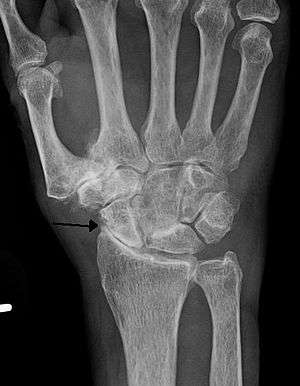

Severe osteoarthritis and osteopenia of the carpal joint and 1st carpometacarpel joint.